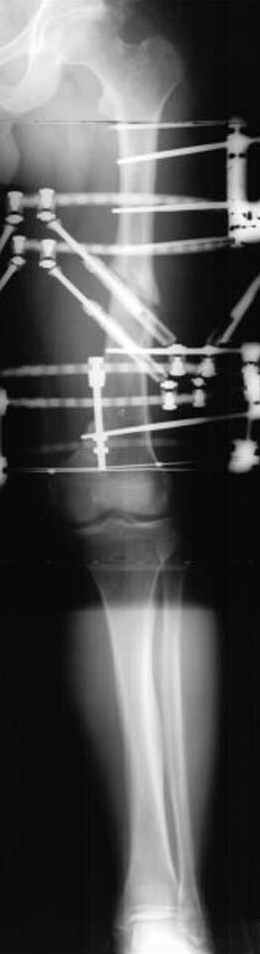

Несколько снимков из моей коллекции, чтобы разьяснить, почему мы до сих пор делаем различные варианты остеотомии.

На рисунке N1 предоперационный план лечения ложного сустава шейки бедра- линия ложного сустава, угол и направление введения импланта, клиновидная остеотомия в градусах и миллиметрах, второй снимок после коррекции, расчет, на сколько удлиняется конечность и размеры импланта;

N3 рисунок окончательный снимок, после операции моя рентгенограмма должен выглядеть примерно как эта картина. На N4 снимке клин перед удалением; N5 послеоперации 3 нед.; N6 окончательная рентгенограмма.

(доложен в Ст. Петербурге 2003 и в Москве 2004)

варус при проксимальном отделе 95 градусной пластиной.

пластическая модель; и коррекция бедра аппаратом Илизарова.